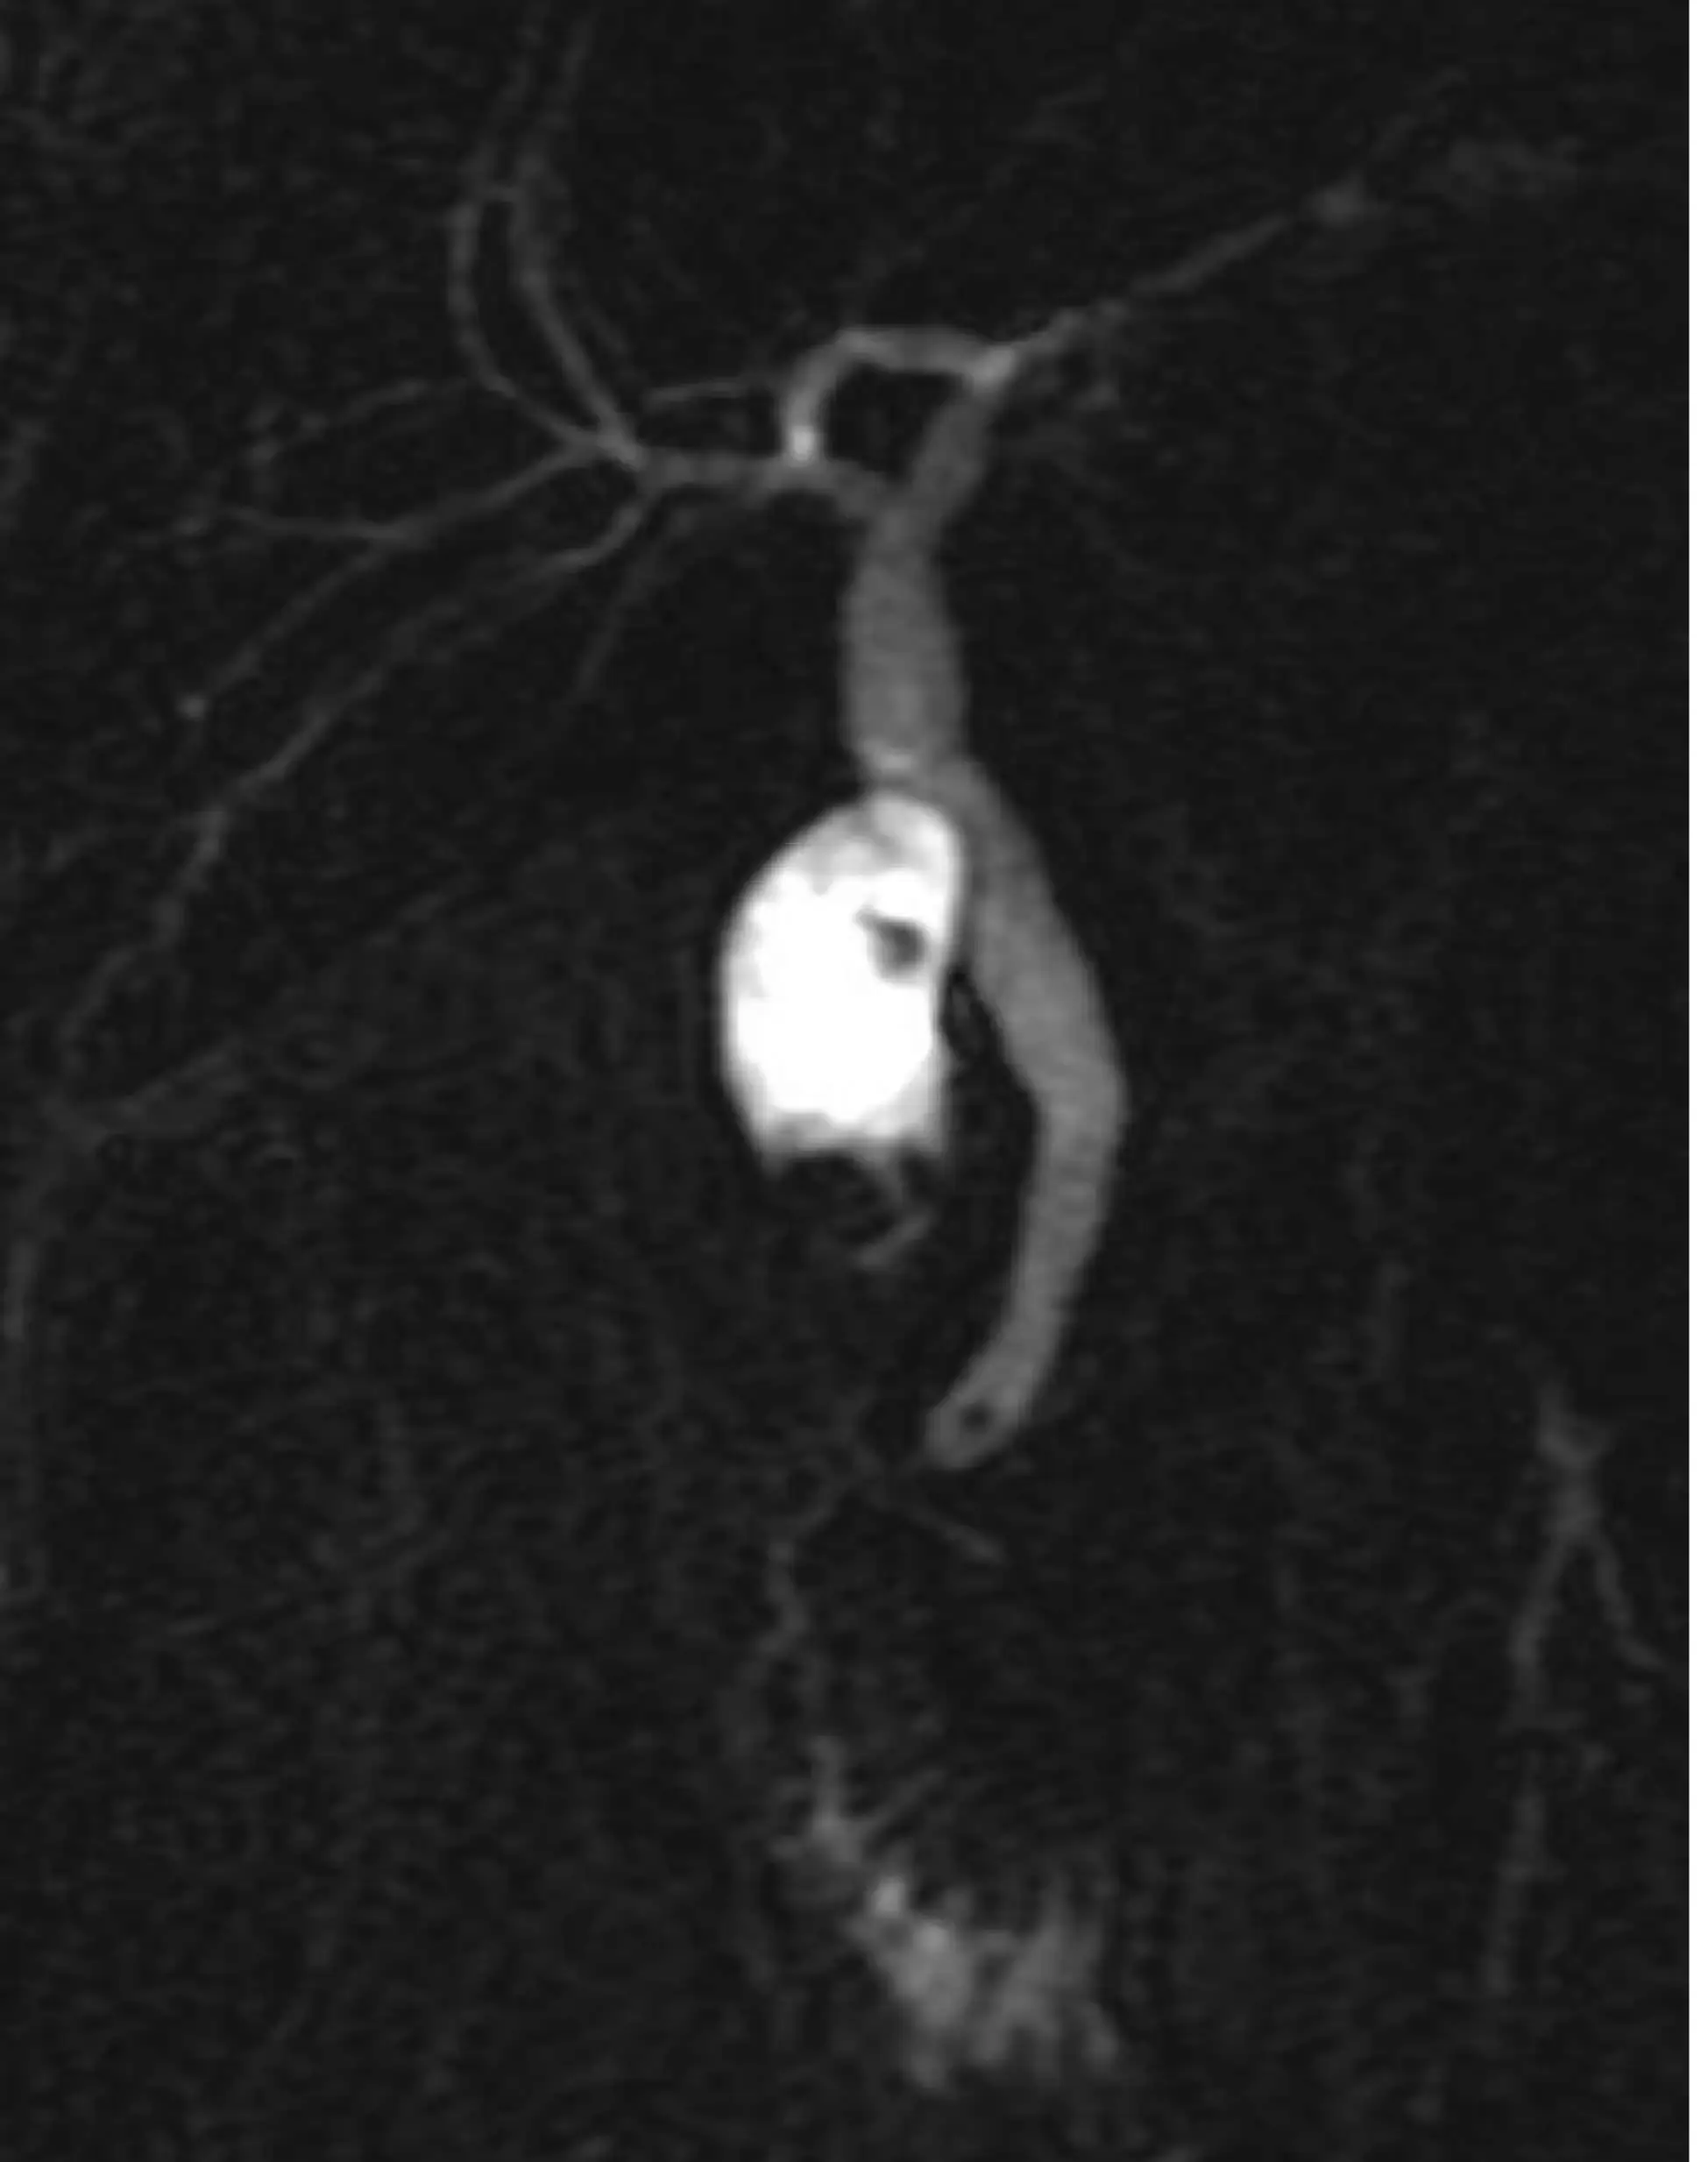

МРХПГ (MRCP)

Бесконтрастная визуализация полости желчного пузыря, внутри и внепеченочных желчных протоков, протока поджелудочной железы.